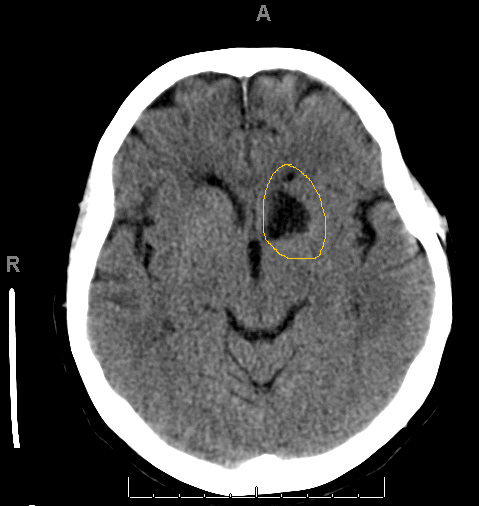

Occlusion of Heubner’s artery sometimes occurs during clipping of an anterior commissure aneurysm, and results in an ischemic infarction of the head of the caudate that manifests in the days after the surgical procedure. The CT image shows an infarct of the caudate possibly as a result of clipping of an ACom aneurysm and sacrifice of the recurrent artery of Heubner.

Figure: infarction of the left artery of Heubner